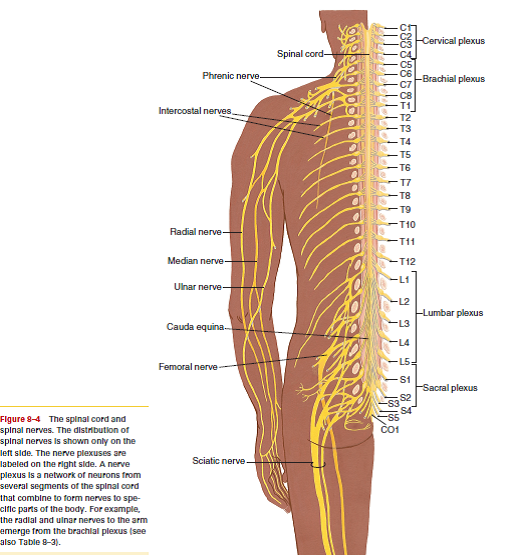

Anatomy of Spinal Cord Injury – Treatment, Complication – Rxharun

Spinal Cord Injury Levels | Bone and Spine | Spinal cord injury, Spinal …

Pin by Michelle Evans on med school | Spinal cord, Spinal nerves …

What is a Spinal Cord Injury (SCI)? – First Aid for Free

Sacrum T8 Spine with Spinal Cord and Nerve Branches

Diagram | Spinal Cord Injury | Pinterest | Spinal Cord Injury and Cords

Spinal Cord Lesions with MS | Multiple experienceS | Spinal cord …

Diagram showing the relationship between spinal nerve roots and …

Pin on A&P – CNS

Pin by Allison Atwill on OT Grad in 2021 | Spinal cord, Spinal cord …

anatomy+of+the+sciatic+nerve | Nerves Of Spine | Healing remedies …

Solved: Where does the spinal cord end? Why is this important c …

spine+diagram | SPINAL NERVES & EFFECTS CHART | Nursing | Anatomia y …